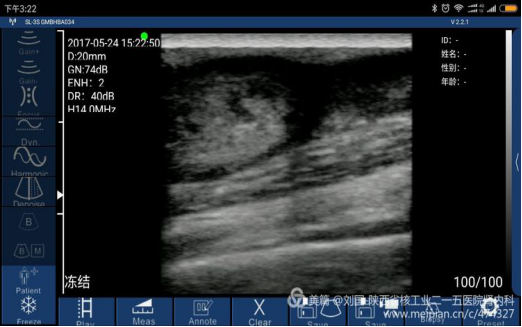

索诺星无线超声所查的结果,显示器是我的小米max。

索诺星的真面目